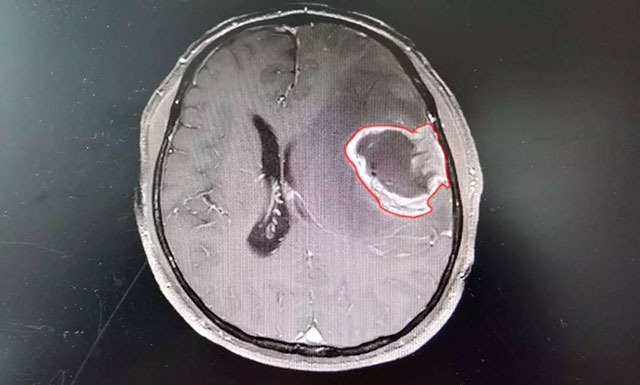

在藍(lán)十字腦科醫(yī)院,頭顱磁共振增強(qiáng)掃描影像進(jìn)一步明確:錢先生左額顳葉占位性病變,類橢圓形團(tuán)塊狀異常信號(hào)大小約4.3*3.2cm,邊界不清,病灶周圍有明顯水腫。從癥狀體征和影像學(xué)資料判斷,錢先生患上腦膠質(zhì)瘤的可能性很大,通過對(duì)患者術(shù)后病理標(biāo)本檢驗(yàn),也印證了該結(jié)論!

▲ 患者術(shù)前磁共振增強(qiáng)掃描影像